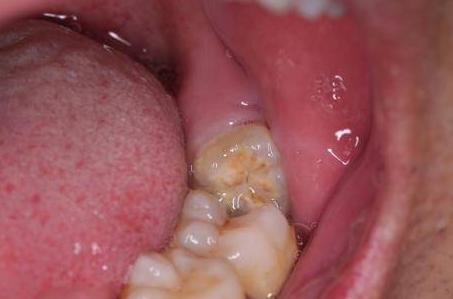

3.智齿引起的牙疼。

如果智齿生长不良并且没有及时拔除,则可能会导致智齿冠周炎,即智齿发炎。此时,表现为诸如肿胀,疼痛,渗出增加,脓液溢出和张口受限的症状。一旦发炎,只能在拔牙之前消除炎症后才能拔除!

治疗方式:消炎后拔牙!